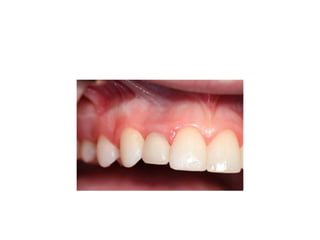

time of insertion

retainer has been modified

final crowns are delivered